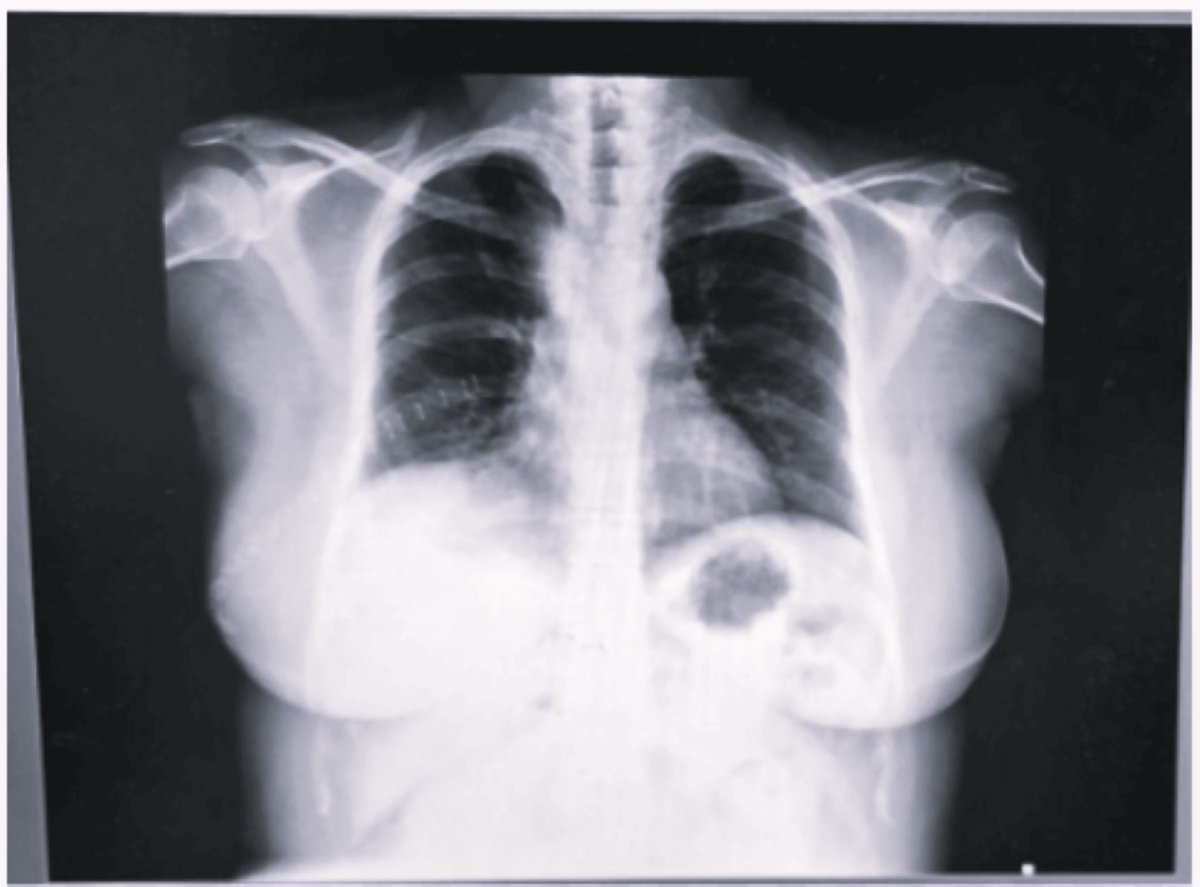

Hey @grok, what is the diagnosis here?